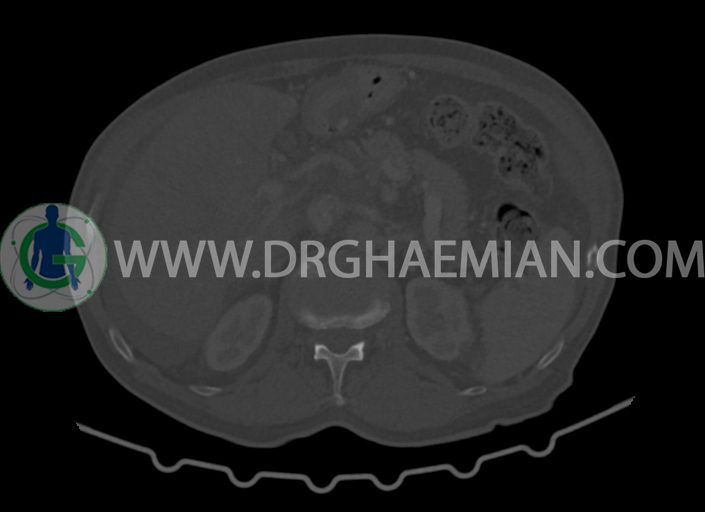

در سی تی اسکن اسپیرال شکم و لگن با کنتراست خوراکی و وریدی (مولتی دیدکتور 16 با مقاطع ظریف و بازسازی های ساژیتال و کرونال) :

کلیه ها کنتراست را ترشح کرده اند و نمای سیستم پیلوکالیسیل و حالب دو طرف نرمال است .

-کیست های کورتیکال ساده در هر دو کلیه به بزرگترین قطر 27mm در سمت چپ (بوسنیاک 1)

-کلسیفیکاسیون آئورت شکمی و شاخه های آن

-توده ی بزرگ با حدود لبوله به ابعاد 89x87x76mm در لوب چپ کبد همراه با گسترش اکستراکپسولار و

شواهد آتروفی لوب جپ کبد

-توده به قطر 33mm در سگمان 6 کبد

-توده ی هیپودنس به ابعاد 30x21mm در ورید پورت خارج کبدی مطرح کننده ی Tumor thrombosis

در ارتباط با ضایعات کبدی در درجه ی اول متاستاز مطرح است. در تشخیص افتراقی با توجه به آتروفی لوب

چپ، mass forming cholangiocarcinoma نیز مطرح می گردد.